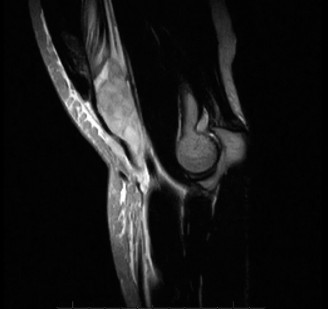

A 45-year-old carpenter presents with shoulder pain that has been ongoing for the last 3 months. He denies any significant injury. He describes night pain and significant discomfort at work. His imaging is shown in Figure 2–9. What is the most likely diagnosis?

Figure 2–9_From Shi LL, Mullen MG, Freehill MT, et al. Accuracy of Long Head of the Biceps Subluxation as a Predictor for Subscapularis Tears. _Arthroscopy 2015;32(4):615–619.

Discussion

The correct answer is (A). Medial subluxation of the biceps tendon as seen in this MRI is commonly associated with a tear of the subscapularis tendon which attaches to the lesser tuberosity. This patient’s pain may in part be attributable to the subscapular tear and this should be evaluated for during physical examination. Supraspinatus tears (Answer B) cannot be easily visualized on axial views and are not associated with medial biceps subluxations. A labral tear and ALPSA lesion (Answers C and D) are not seen on the images provided. The question stem and MRI are not suggestive of shoulder instability (Answer E). Objectives: Did you learn...? Diagnose and treat acute rotator cuff tears?

Which of the following findings is indicative of a subscapularis tendon tear?

The answer is (B). As the four layers of the lateral rotator interval insert onto the lesser tuberosity of the humerus, they form the “reflection pulley” that forms a sling around the tendon of the long head of the biceps before it enters the bicipital (intertubercular) groove. A tear of the upper part of the subscapularis can disrupt this reflection pulley and destabilize the biceps tendon, allowing it to sublux or even

dislocate out of its groove, usually in a medial direction. If this happens, the intertubercular groove will be empty on MRI. Often, a “pulley sign” will also be seen on MRI when this occurs. This is when contrast material extravasates extra-articularly just over the superior border of the subscapularis tendon on axial images (see Fig. 2–11).

Figure 2–11_Axial T1 MRI. Left: an empty intertubercular sulcus, positive pulley sign (straight _black arrow on left), and dislocated biceps tendon (curved black arrow). Right: fraying subscapularis tendon (arrow). (From Lyons RP, Green A. Subscapularis tendon tears. J Am Acad Orthop Surg. 2005;13(5):353–363.)